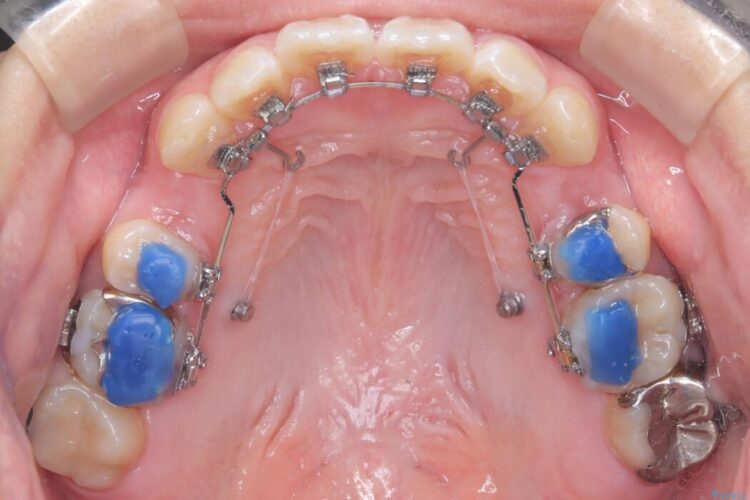

- 矯正装置:ハーフリンガル矯正

装置は人目を気にせず治療できるよう、上顎に裏側矯正、下顎に表側矯正を組み合わせたハーフリンガル矯正を提案しました。

装置には、上顎には目立たない裏側矯正(舌側矯正)を、下顎には透明な審美ブラケットを使用するハーフリンガル矯正を採用しました。抜歯によってできたスペースを最大限に活用し、前歯を効率よく後方へ移動。治療の結果、口元の突出感が大幅に解消され、Eライン(横顔の美しさの基準)も改善しました。人目を気にすることなく治療を完遂し、自信の持てる美しい横顔を獲得していただけました。